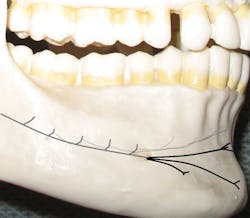

Figure 2: Mental foramen

Since only the soft tissues are anesthetized by the mental block, the incisive block is preferred for nonsurgical periodontal therapy procedures. The mental foramen, which opens anteriorly and superiorly, is usually located near the apex of the second premolar (see Figure 2), although studies indicate that it can be located from the distal of the canine to the first molar.3-5 It is advisable to check the radiographs and palpate the area prior to procedures to determine its location. The foramen appears as a round or oval radiolucency on radiographs (see Figures 3, 4) and may be palpable as a concavity or rough elevation.2